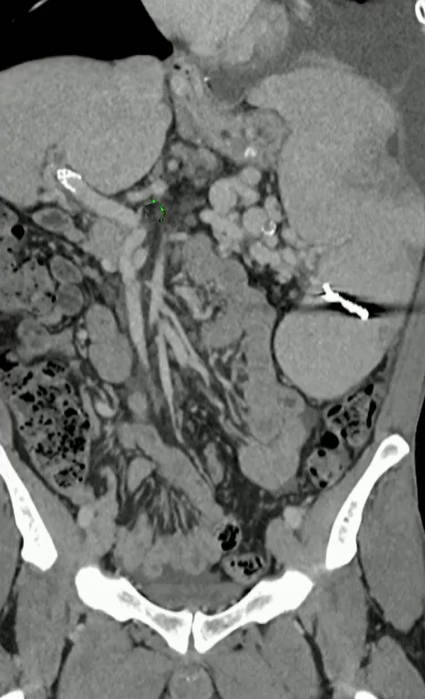

50岁 男性, 外科医生,25 年前的 PVT;目前胸水,工作繁重,生活受限,每周一次胸水引流,由于慢性肺静脉血栓形成而进行的移植手术

步骤: 鉴于慢性血栓形成的复杂性: 一种经脾脏途径的门静脉再通术(PVR)。 随后是经颈静脉肝内门体分流术 。

结果:术后影像学检查显示门静脉和脾静脉的血流情况有所改善,且残留血栓极少。

通过经颈静脉肝内门体分流术(TIPS)治疗慢性门静脉血栓时所涉及的技术复杂性和决策难题,尤其是在标准方法因血栓程度过重而无法实施的情况下更是如此。 采用脾经脏穿刺术治疗门静脉高压症的方法证明能够有效克服这些难题,从而成功实施了经颈静脉肝内门体分流术(TIPS)。 PVR-TIPS 作为一线治疗方案:PVR-TIPS 为慢性门静脉血栓的治疗提供了一种技术上可行的解决方案,克服了标准 TIPS 安装所面临的难题。 持久效果:该干预措施不仅恢复了门静脉的血流,而且在后续随访中还显示出持续的通畅性以及血栓的完全消散。